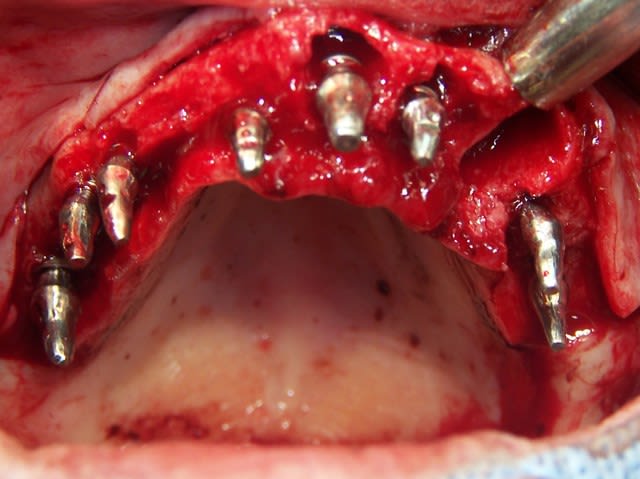

Eu pratiquant une mise en charge légèrement ou différée tu perds tous les avantages de la mise en charge immédiate. Le protocole de mise en charge immédiate POSITDENTAL est maintenant éprouvé, inévitablement il requiert une bonne maîtrise de l’implantologie. La passivité et précision du bridge se faont lors de la mise en place.

Vidéo d'une mise en charge immédiate: